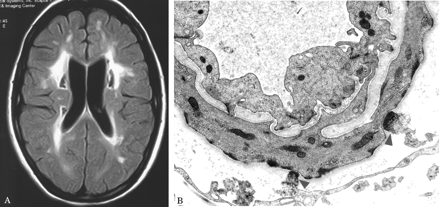

一名48岁的女性被认为在神经病学Baystate医学中心咨询步态首页不稳和大脑的异常的CT扫描。她有中风病史5年之前由奔袭弱点没有残留症状。她在遥远的过去,历史还包括癫痫先兆型偏头痛和抑郁症。认知障碍的神经系统检查是引人注目的证据,构音障碍的演讲,和快速反应能力。核磁共振成像的大脑。有弥漫白质异常hyperintensity组成的T2和fluid-attenuated inversion-recovery(天赋)成像和囊性变化(图一个)。研究结果提示大脑常染色体显性动脉病与皮层下梗死和白质脑病(CADASIL)。1皮肤活检显示特征颗粒沉积在基板的一个小血管电镜(图B)。2她后来发现有一个Notch3基因突变。